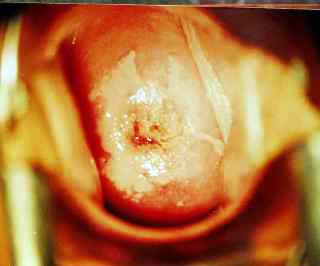

Aκολουθούν δύο τυπικά περιστατικά με κολποσκοπική εικόνα προσβολής του τραχήλου μήτρας απο HPV. Αρνητική περιοχή σε οξικό οξύ και lugol. Χωρίς τις δοκιμασίες αυτές ο τράχηλος εντυπωσίαζε φυσιολογικός. Το κυτταρολογικό επίχρισμα κατά Papanicolaou ήταν και στις δύο περιπτώσεις αρνητικό. Στην μικροβιοψία προέκυψε ιστολογικώς εικόνα που συνηγορουσε για HPV

Δοκιμασία οξικου οξέως. Αρνητικη περιοχη, μωσαϊκο

Δοκιμασία οξικου οξέως. Αρνητική περιοχή με εικόνα μωσαΪκού